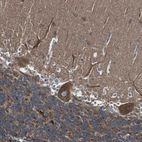

Immunohistochemical staining of human Cerebellum shows strong cytoplasmic positivity in Purkinje cells.